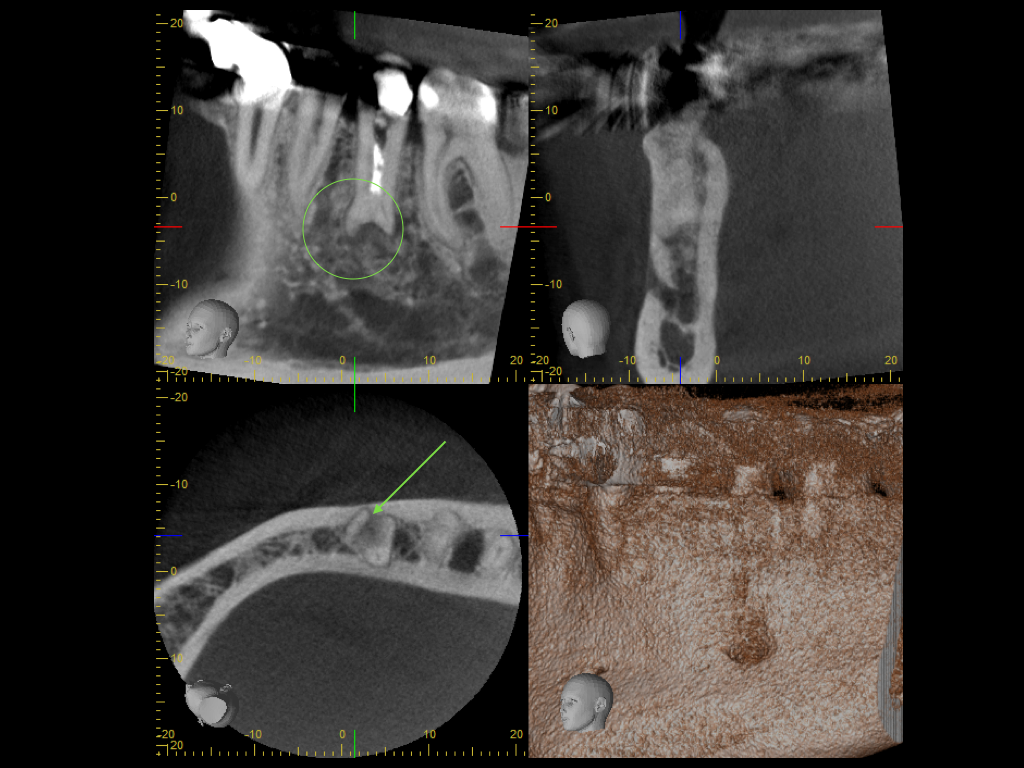

DVT.001

2015 Fallvorstellung 1